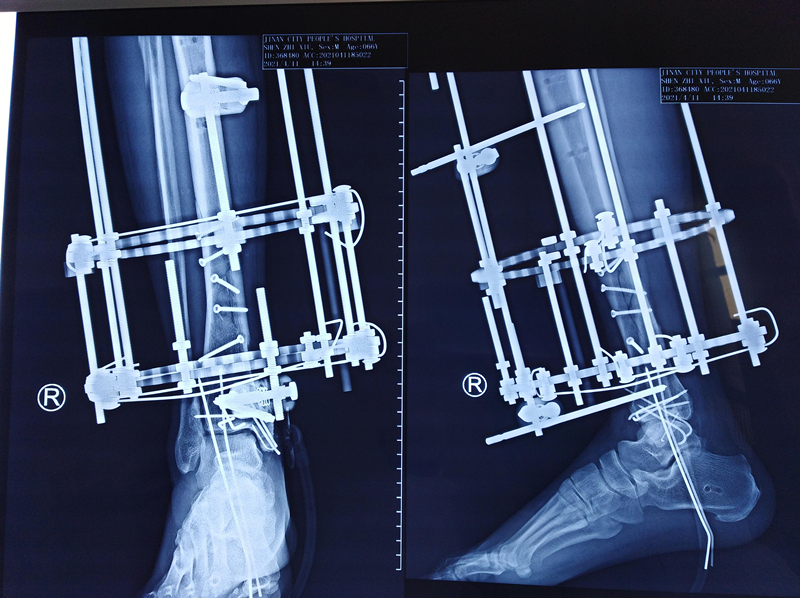

第二次手术拍片

第三次手术图片